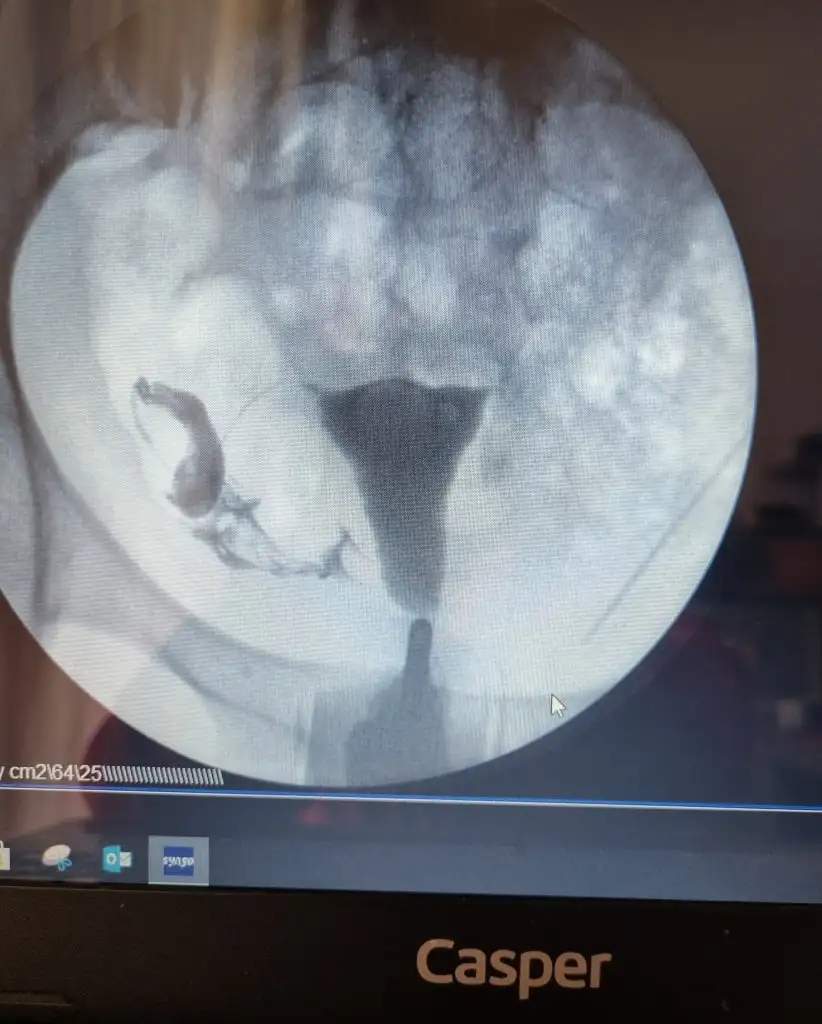

• image.webp

image.webp

71 KB · Görüntüleme: 111